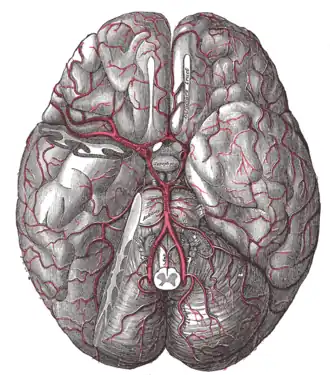

Кровоснабжение гипофиза осуществляется из верхних и нижних гипофизарных артерий, являющихся ответвлениями внутренней сонной артерии. Верхние гипофизарные артерии вступают в воронку гипоталамуса и, проникая в мозг, разветвляются в первичную гемокапиллярную сеть; эти капилляры собираются в портальные вены, которые направляются по ножке в переднюю долю гипофиза, где снова разветвляются на капилляры, образуя вторичную капиллярную сеть. Нижние гипофизарные артерии снабжают кровью преимущественно заднюю долю. Верхние и нижние гипофизарные артерии анастомозируют друг с другом. Венозный отток происходит в пещеристые и межпещеристые синусы твёрдой мозговой оболочки.

Гипофиз получает симпатическую иннервацию от сплетения внутренней сонной артерии. Кроме того, в заднюю долю проникают множество отростков нейросекреторных клеток гипоталамуса.